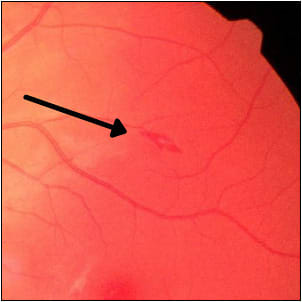

Although the patient was not fully conscious during the seizures, her electroencephalogram findings were normal. She had been diagnosed with psychogenic nonepileptic seizures 3 years prior as well as with postural orthostatic tachycardia syndrome (POTS). Ophthalmic findings were normal except for mild punctate corneal epithelial ero sions in both eyes and a white-centered hemorrhage in the left eye just superior to the macula on fundoscopic exam (Figures 1 and 2).

Roth-like spots and nonepileptic seizures combined with episodes of angular cheilitis and seborrheic dermatitis led to suspected pyridoxine deficiency. Forty-eight hours after daily pyridoxal-5'-phosphate 100 mg, the seizures resolved with the Roth-like spot almost completely resolving in 4 days. The underlying cause of this patient’s vitamin B6 malabsorption was lymphocytic colitis likely secondary to Sjogren syndrome. Vitamin B6 deficiency should be considered as part of the differential diagnosis in patients with psychogenic nonepileptic seizures and in white-centered hemorrhages of unknown origin.